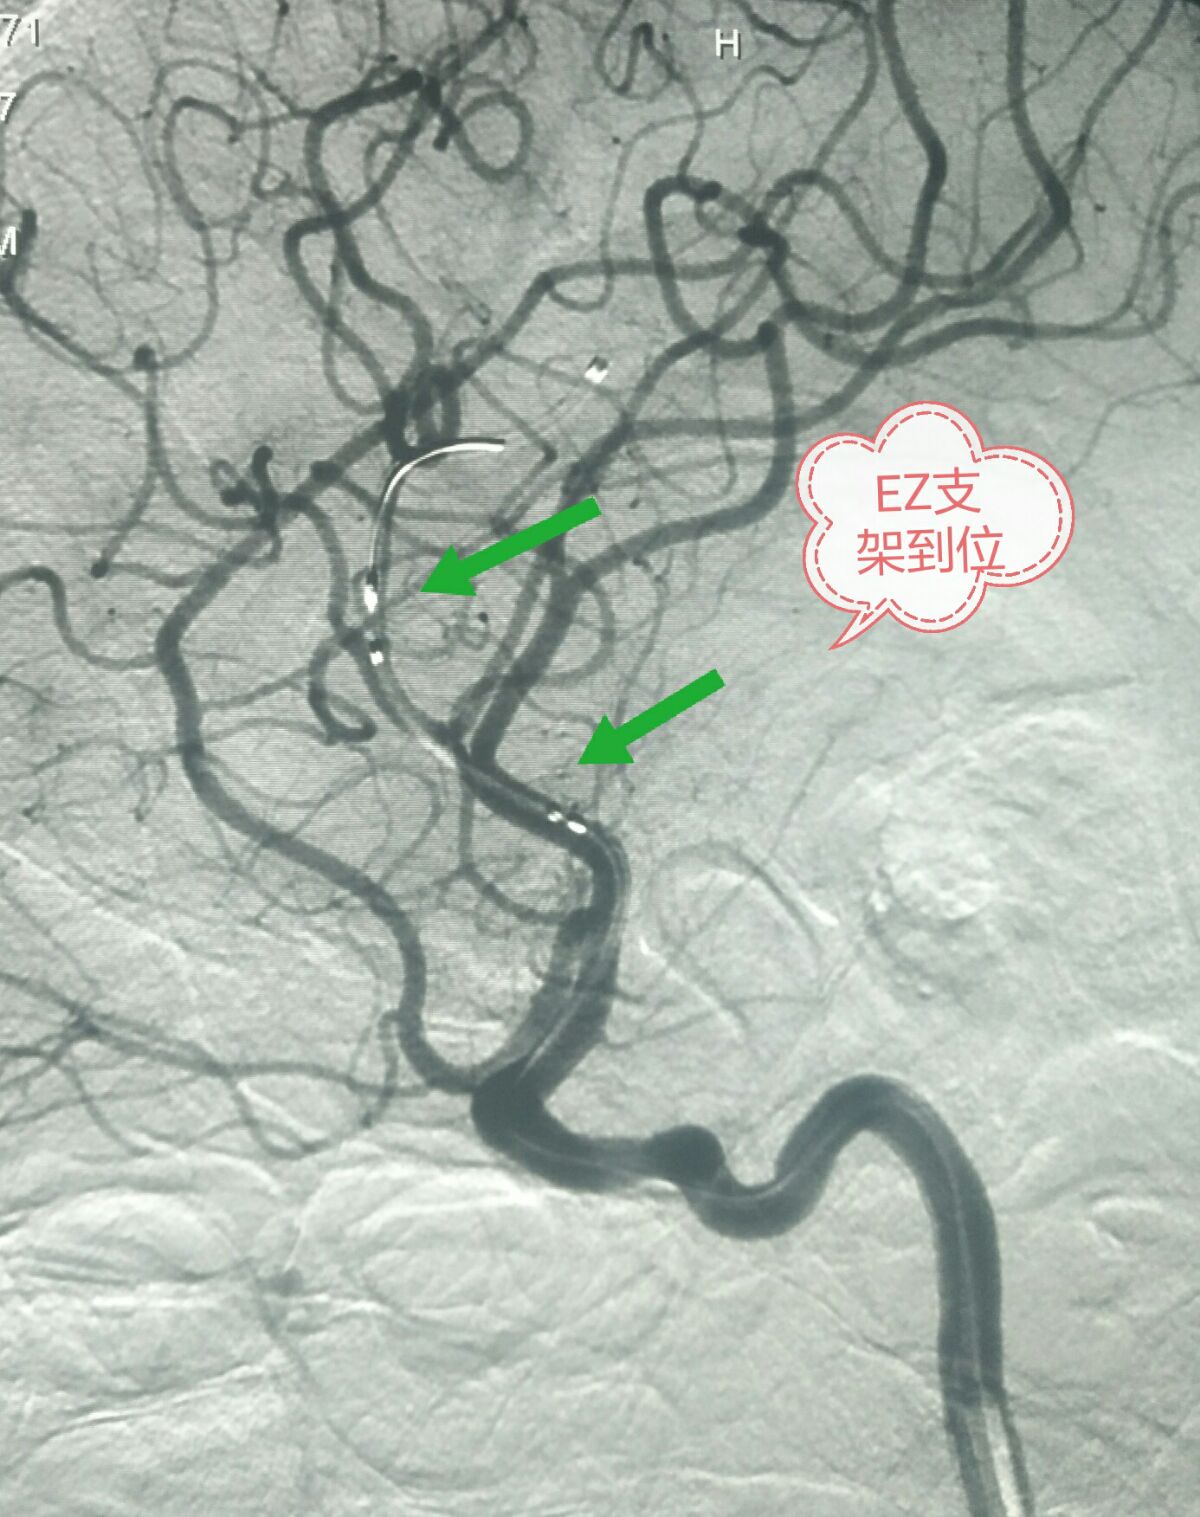

同轴交换XT-27微导管到达M3段,2.5*15的EZ支架到位